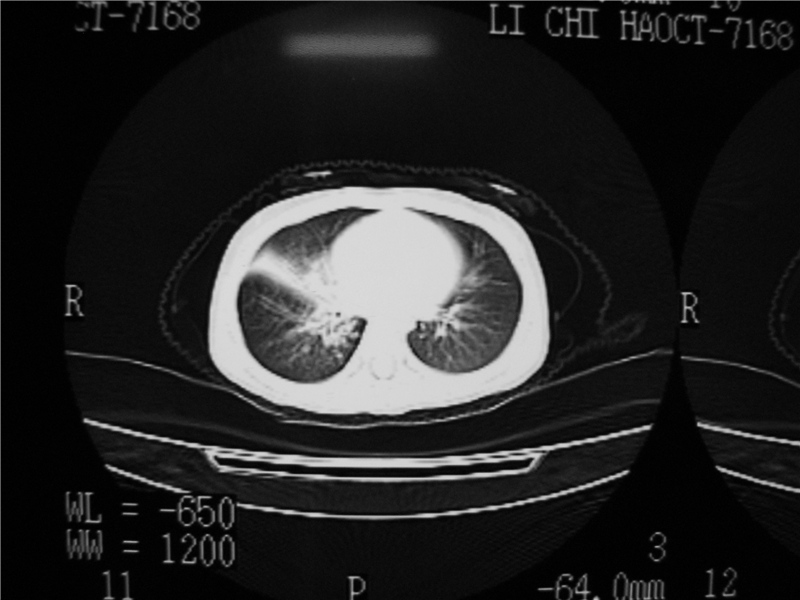

标题: PED3236:男2岁进食花生米后发烧10天。

右肺中叶及下叶内段大片实变密度增高影,可见支气管气象,肺炎.

摄吸气及呼气相对比片,本例为有肺中叶阻塞性炎症、不张,右肺下叶阻塞性炎症。

右侧中间段支气管阴性异物可能,建议支气管镜

1)右肺炎症并右肺中叶肺不张,右肺上叶充气不良。2)右侧支气管异物不排除。

结合病史,考虑气管异物所致。

再有,我们16排ct有气管重建功能,肯异物效果可以。

结合临床考虑支气管异物并阻塞性肺炎、肺不张。